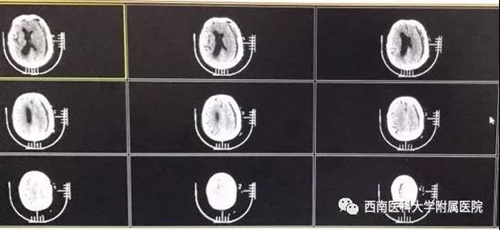

术前的CT片

“打电话的老人78岁了,幸好会微信。”通过微信传来的照片,黄昌仁大致了解了病人的病情,是颅内慢性硬膜下血肿,“通过手术,是可以救治的。”

术后的CT片